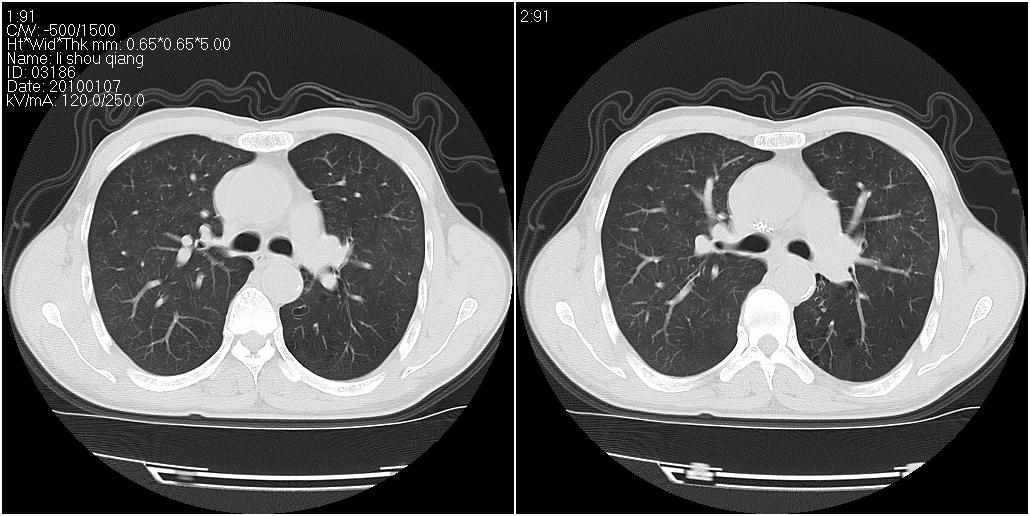

标题: CT24038:男性,58岁。主因咳嗽带血性CT检查。 [打印本页]

标题: CT24038:男性,58岁。主因咳嗽带血性CT检查。

右肺中叶外侧段见一不规则的软组织肿块,边缘可见毛刺,并见厚壁空洞,与胸膜分界欠清。另左下肺见多个小囊状扩张区

右肺中叶外侧段可见团块影,外形不规则,内见空泡征。左下肺见蜂窝状低密度透亮影,部分层面主动脉旁瘤样突出。考虑右肺中叶外围型肺癌可能性大,左下肺支气管扩张,主动脉弓瘤样突出。

1)考虑右肺中叶周围型肺癌并癌性空洞形成。2)左肺下叶支气管扩张可能性大。

支持1)考虑右肺中叶周围型肺癌并癌性空洞形成。2)左肺下叶支气管扩张可能性大。